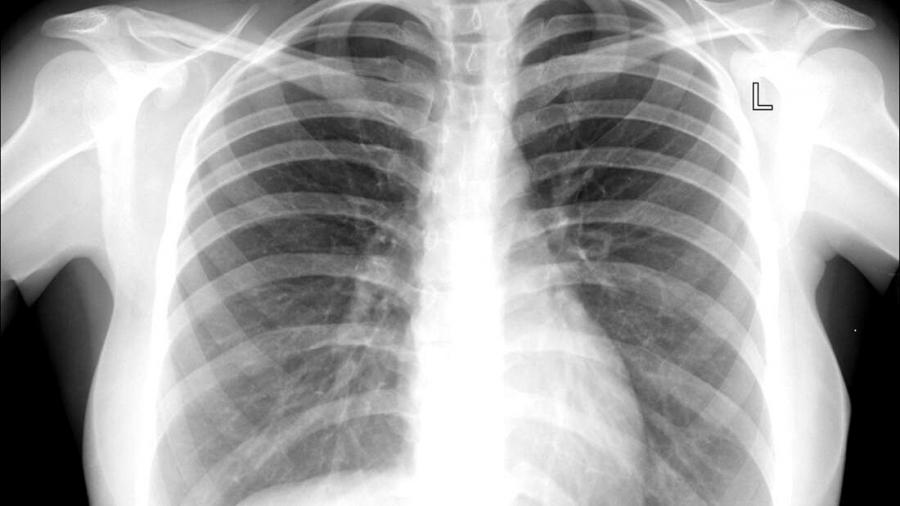

Слюнката на младата учителка е тествана за туберкулоза – резултатът е отрицателен. След като сканират гръдния ѝ кош обаче, лекарите откриват лезия в горния лоб на дробовете ѝ. По-задълбочени проучвания показват, че става дума за „обърната наопаки структура, наподобяваща торба, която е заседнала в бронхите.“